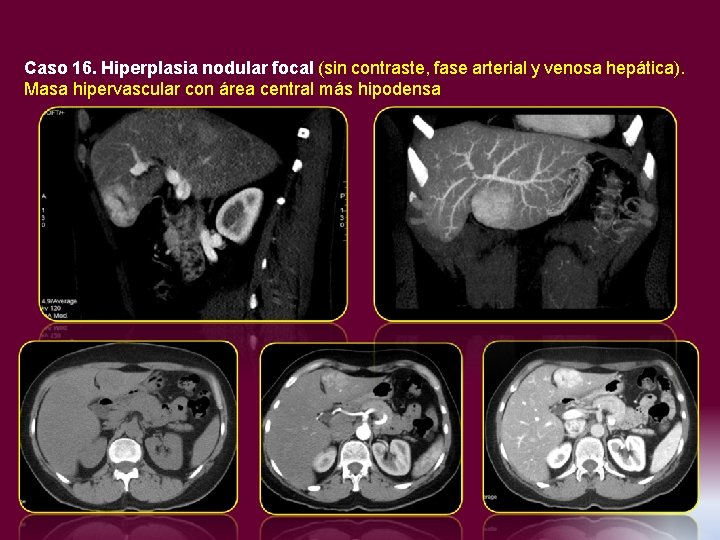

Caso 16. Hiperplasia nodular focal (sin contraste, fase arterial y venosa hepática). Masa hipervascular

Caso 16. Hiperplasia nodular focal (sin contraste, fase arterial y venosa hepática). Masa hipervascular con área central más hipodensa